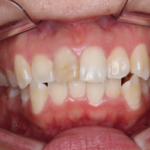

【空隙歯列、叢生】インビザライン症例:隙間とガタガタが気になる

治療前 治療後 症例の詳細 主訴 隙間とガタガタが気 ...